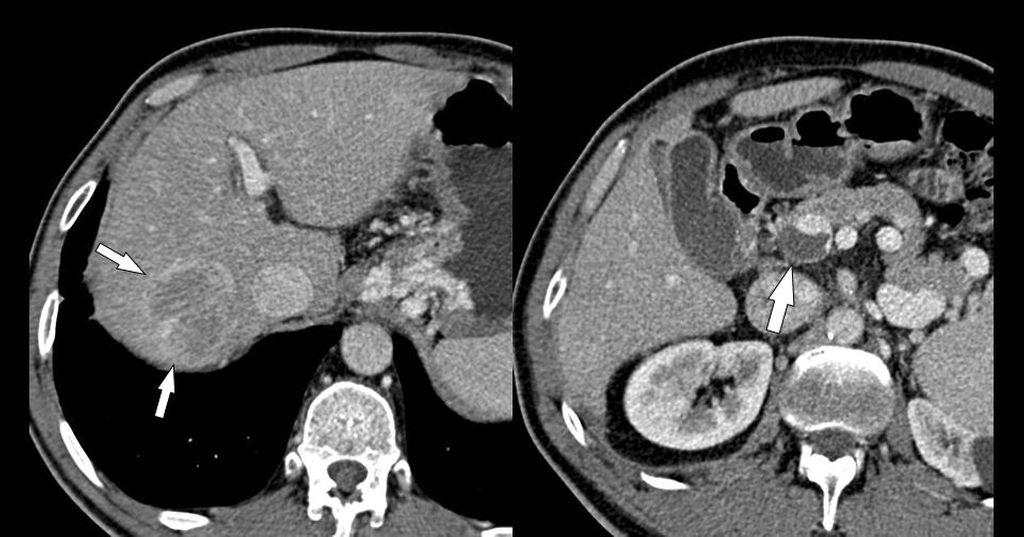

Abb. 1: Die farbcodierte Duplexsonografie zeigt einen wandständigen (nichtokklusiven) Thrombus (Pfeil) in der perfundierten Pfortader

Die bildgebende Diagnostik stützt sich auf die farbcodierte Duplexsonografie (Abb. 1), die Kontrastmittel-verstärkte MDCT (Abb. 2) und die MRT, wobei die MDCT die höchste Aussagekraft hinsichtlich Ausdehnung der PVT und Darstellung möglicher Komplikationen hat. Wichtig ist bei der MDCT die Anfertigung von 3D-Rekonstruktionen des MDCT-Datensatzes zur besseren Darstellung der Thromboseausdehnung (Abb. 2), im Vergleich zur ausschließlichen Darstellung auf axialen Bildern.